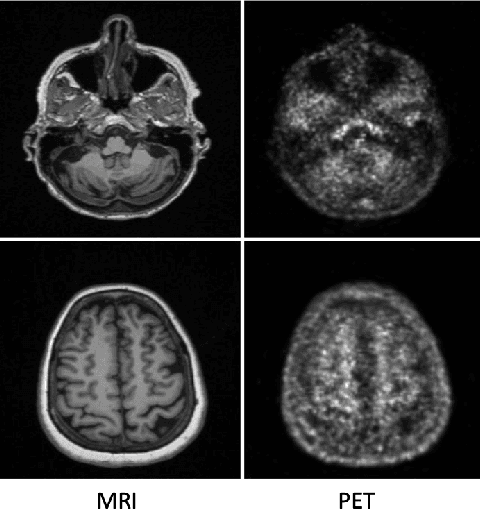

Abstract:While Positron emission tomography (PET) imaging has been widely used in diagnosis of number of diseases, it has costly acquisition process which involves radiation exposure to patients. However, magnetic resonance imaging (MRI) is a safer imaging modality that does not involve patient's exposure to radiation. Therefore, a need exists for an efficient and automated PET image generation from MRI data. In this paper, we propose a new frequency-aware attention U-net for generating synthetic PET images. Specifically, we incorporate attention mechanism into different U-net layers responsible for estimating low/high frequency scales of the image. Our frequency-aware attention Unet computes the attention scores for feature maps in low/high frequency layers and use it to help the model focus more on the most important regions, leading to more realistic output images. Experimental results on 30 subjects from Alzheimers Disease Neuroimaging Initiative (ADNI) dataset demonstrate good performance of the proposed model in PET image synthesis that achieved superior performance, both qualitative and quantitative, over current state-of-the-arts.